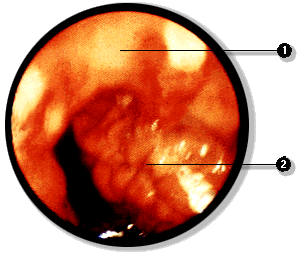

Mediante la esofagoscopía es posible pesquizar várices esofágicas y mediante la rectoscopía es posible pesquizar hemorroides, signos estos dos de hipertensión portal.